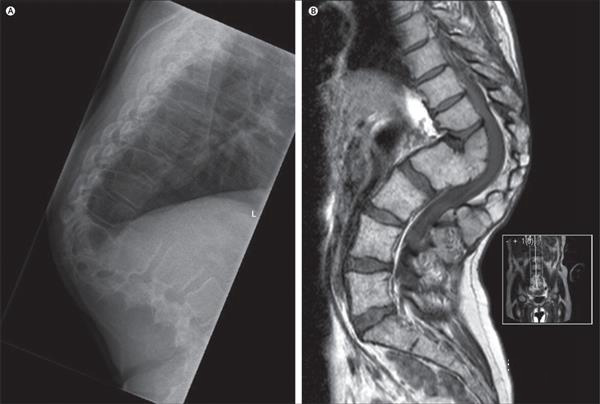

那么,醫(yī)生們是如何完成3D打印鈦?zhàn)倒堑哪?他們首先獲得了受損脊柱的CT和MRI掃描,然后再用3D設(shè)計(jì)軟件將這些掃描轉(zhuǎn)換成可打印的鈦?zhàn)倒悄P?,并用一臺(tái)金屬3D打印機(jī)將其打印出來。打印完成后,他們還對(duì)3D打印植入物進(jìn)行了進(jìn)一步的測(cè)試,并向印度、瑞典和美國的設(shè)計(jì)團(tuán)隊(duì)尋求幫助。